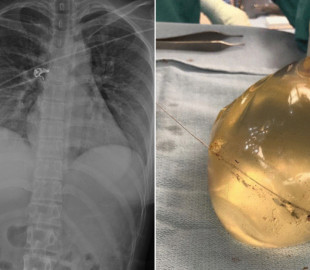

Хиймэл хөх амь насыг нь аварчээ